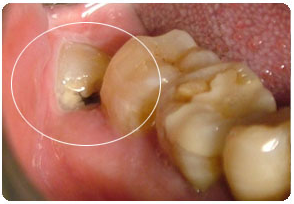

位置不正(阻生智齿)。这种时候一般需要牙医拍片得知,但患者会感觉到不适或牙疼。更有甚者由于空间不足,智齿生长过程中挤压邻牙,使得原本一口整齐的牙,变的歪歪扭扭。

不易清洁的智齿。智齿常长的歪七扭八,难以清洁到位,极易形成蛀牙。此时可以提前拔除。